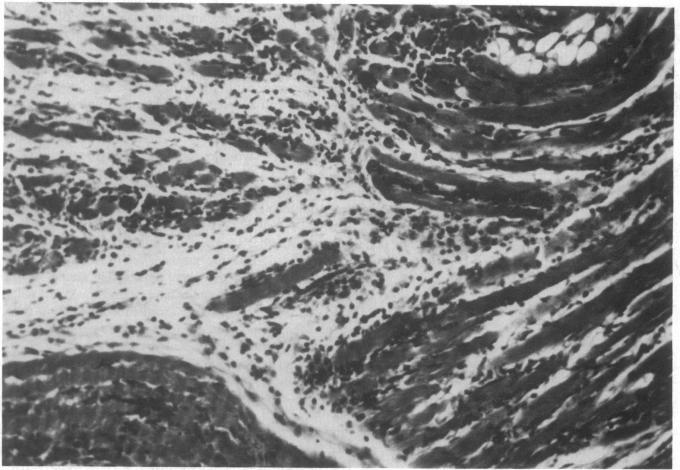

Chronic inflammatory myositis similar to human polymyositis occurs in mice after infection with a strain of Coxsackievirus B 1 (CVB 1). To investigate the role of T cells in the pathogenesis of this disorder, we compared disease expression in T cell-deficient athymic nude (nu/nu) mice and heterozygotes (nu/+) with normal T cell function. Acute infectious myositis occurred in nu/nu and nu/+ mice. Chronic (greater than 21 d postinfection) weakness and myositis, however, developed only in nu/+. Resistance to disease in nu/nu mice was not explained by insusceptibility to infection; the amount of virus lethal for 50% of mice and virus replication were comparable in both groups. Additionally, anti-CVB 1 antibody production was similar in both groups. Reconstitution of infected nu/nu mice with spleen cells from normal mice resulted in disease. These results demonstrate that chronic weakness after infection with this virus is not simply a sequela of acute myonecrosis and suggest that T cells play a pivotal role in the pathogenesis of chronic myositis.

感染柯萨奇病毒B1(CVB1)毒株后,小鼠会出现类似于人类多发性肌炎的慢性炎症性肌炎。为了研究T细胞在这种疾病发病机制中的作用,我们比较了T细胞缺陷的无胸腺裸鼠(nu/nu)和具有正常T细胞功能的杂合子(nu/+)小鼠的疾病表现。急性感染性肌炎在nu/nu和nu/+小鼠中均有发生。然而,慢性(感染后超过21天)肌无力和肌炎仅在nu/+小鼠中出现。nu/nu小鼠对疾病的抵抗力并非由于对感染不敏感所致;两组中对50%小鼠致死的病毒量和病毒复制情况相当。此外,两组中抗CVB1抗体的产生情况相似。用正常小鼠的脾细胞重建感染的nu/nu小鼠会导致疾病发生。这些结果表明,感染该病毒后的慢性肌无力并非仅仅是急性肌坏死的后遗症,提示T细胞在慢性肌炎的发病机制中起关键作用。